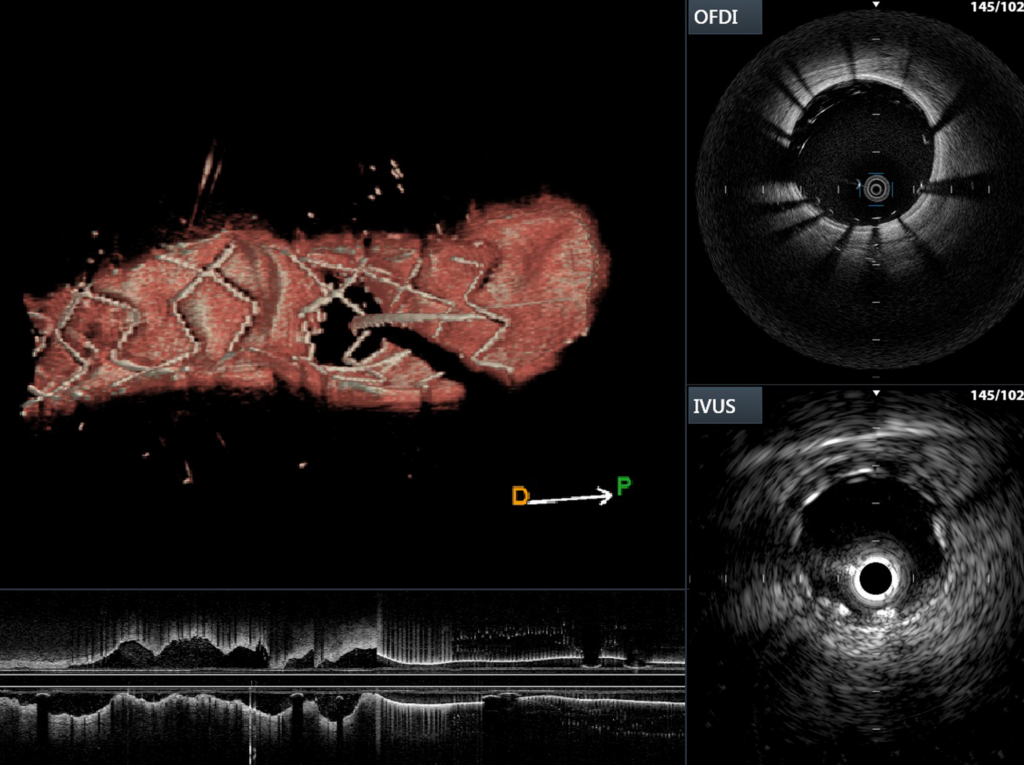

Επίσης, η ενδοαγγειακή απεικόνιση μας δίνει πολύτιμες πληροφορίες με μια πολύ εξειδικευμένη προσέγγιση για τον ασθενή. Μελέτες έχουν δείξει ότι οι τεχνολογίες αυτές, όπως ο ενδοαγγειακός υπέρηχος (IVUS) και η οπτική τομογραφία συνοχής (OCT), βελτιστοποιούν τα αποτελέσματα σε «σύμπλοκες» ανατομικά στενώσεις και περιστατικά. Επίσης, μας δίδεται η δυνατότητα να ανιχνεύουμε ευάλωτες («επικίνδυνες») αθηρωματικές πλάκες, ή ανατομικές ιδιαιτερότητες εκ των προτέρων, οδηγώντας σε εξατομικευμένη προσέγγιση, πιο σωστές αποφάσεις και καλύτερο μακροχρόνιο αποτέλεσμα για τον ασθενή μας.